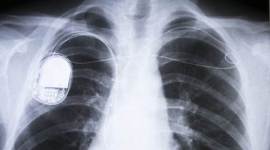

Pacemakers are usually given to those who have lived a long life and now their heart needs an extra assistance. For me, I was born with a heart defect," Shree, 26, wrote.